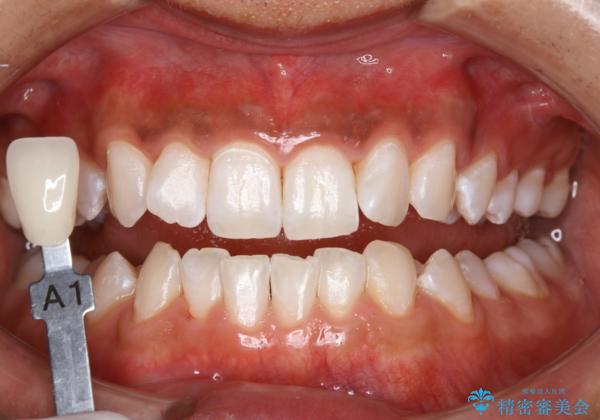

- 歯を白くしたいとのことでした。

オフィスホワイトニング(TION Whitening・処置前クリーニング込み)コースを行いました。

処置後は艶のある綺麗な白さになりました。